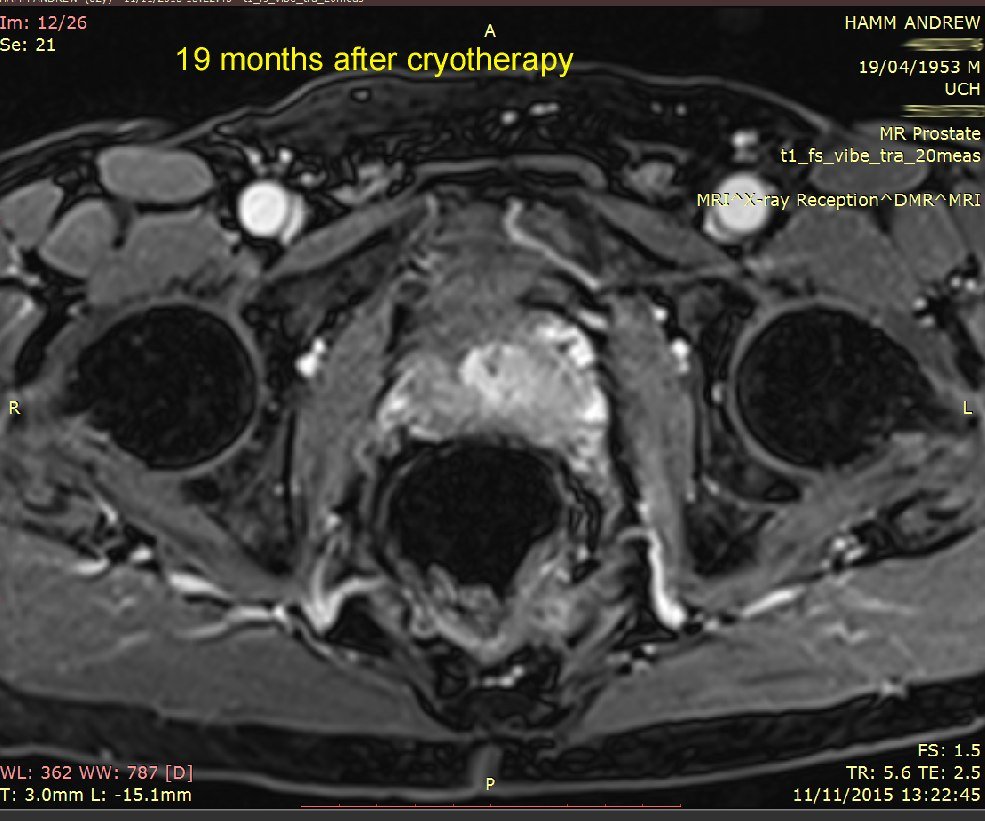

I've put 3 MRI images taken in November 2015. Compare these with my earlier ones below that, from 24 November 2014. Whilst not commenting specifically on these, the consultant said that the overall MRI had not revealed any significant (observable) prostate cancer.

18-day and 7-month MRI and PSA comparison - see image below.

Explanation: my prostate is roughly outlined in RED.

The original location of the tumour is roughly outlined in YELLOW on the 18-days image.

The ablated area is outlined in GREEN on the 18-days image.

These results show:

The ablated area has shrunk to (I presume) no volume at all.

My prostate volume has reduced by 5cc, which is pretty close to the 5cc volume that Emberton estimated would be ablated.

My PSA has rougly HALVED. The present PSA of 3.1 is within the range expected for a man of my age (61 years) who does not have significant prostate cancer.

My conclusion: Success! Cancer treated*.